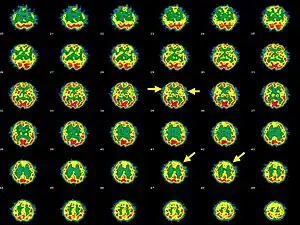

| Brain SPECT transaxial images of a patient afflicted with Hashimoto's encephalopathy. | |

- Single photon emission computed tomography shows focal and global hypoperfusion (75% of cases)